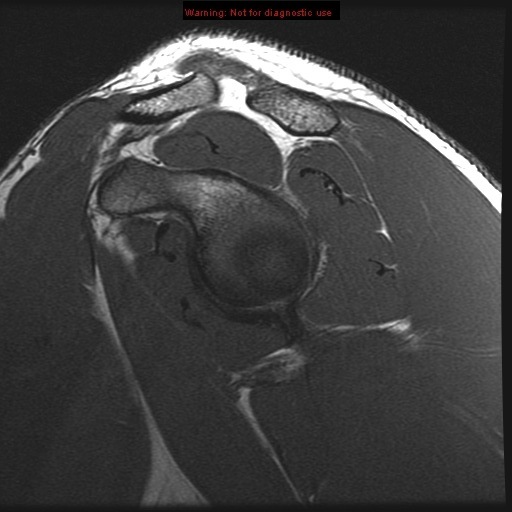

subscapularis muscle

supraspinatus muscle

infraspinatus tendon

glenoid labrum subscapularis muscle

deltoid muscle posterior belly supraglenoid tubercle